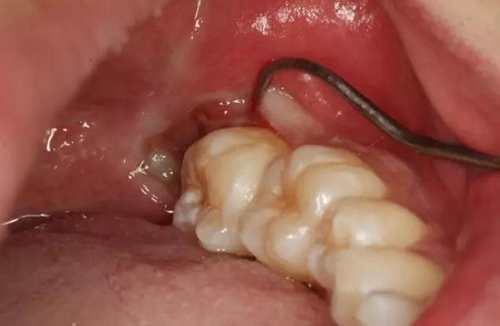

圖3.張口一指半的情況下,進(jìn)行下牙槽神經(jīng)阻滯麻醉。

圖4.38頰側(cè)牙齦腫脹、探診出血

圖5探診分離牙齦